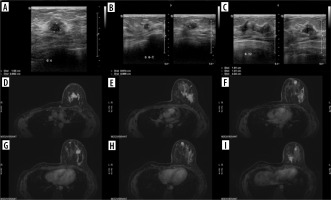

A 14-year-old patient had a lump in her right hand for 7 months, between the first and second metacarpal bones, which was initially assessed as a ganglion. The lesion was finally resected, and histopathological results revealed embryonal partial alveolar RMS. The girl was transferred to our centre for qualification for treatment. In the meantime, she felt a lesion/lump in the right breast. US revealed a nodular lesion 28 × 15 × 28 mm at 12 o’clock with irregular outlines and heterogeneous echostructure (Figure 7), as well as one larger hypoechoic lymph node and several smaller ones in the right axilla.

Figure 7

Ultrasound of right breast metastasis in Patient no. 3. A) Axial and sagittal plane. B) Colour Doppler, axial plane

On PET-CT, the breast lesion and the larger axillary lymph node showed increased tracer uptake. A biopsy was performed, which confirmed the metastatic nature of these lesions. During treatment (chemotherapy regimen CEVAIE, i.e. alternating cycles of CEV [carboplatin, epirubicin, vincristine], IVA [ifosfamide, vincristine, actinomycin], IVE [ifosfamide, vincristine, etoposide]; the patient was switched from vincristine to vinblastine after cycle 1 due to neurotoxicity of vincristine) remission of metastases was achieved. The patient was qualified for a right mastectomy with lymphadenectomy followed by radiotherapy (on the tumour bed in the right hand and the lymph nodes of the right axilla – a total of 5000 cGy/t in 25 fractional doses of 200 cGy/t) and maintenance chemotherapy. After approximately 5 months, new lumps were found in the left breast, which turned out to be further metastases. US (Figures 8A-C) and MRI revealed numerous focal contrast-enhancing lesions (Figures8 D-I); the biggest one (35 × 15 mm) was located at 12 o’clock.

Figure 8

Exams show the progression of the disease in Patient no. 3 with metastases in the left breast. Ultrasound: A) nodule at 4 o’clock, axial plane; B) nodule at 6:30 o’clock, axial and sagittal plane; C) nodule at 12 o’clock, axial and sagittal plane. D-I) Breast MRI. Status after right mastectomy. Numerous lesions in left breast. D-I) VIBRANT/T1 post-Gd, axial plane

Second-line treatment consisting of CBDCA (carboplatin) and Topo (topotecan) was initiated; however, progression of breast lesions was detected. The patient was qualified for a left-sided mastectomy with resection of the pectoral muscle and lymph nodes. Histopathological examination confirmed RMS. Despite further treatment (PACE: cisplatin, Adriamycin, cyclophosphamide, etoposide), metastasis in the paravertebral area at the T9-Th10 level was found. Ultimately, the patient died due to complications of chemotherapy – pulmonary mycosis, after 3 years of disease.

Case 4

The parents of a 10-year-old girl noticed a painless lump about 1.5 cm in diameter on her left foot. Over the next 5 months, the lesion gradually enlarged, and lumpy lesions appeared in both breasts. An outpatient US of the left foot was performed showing a tumour of 45 × 24 × 30 mm at that time, with solid-cystic structure; breast US confirmed nodular lesions. MRI of the foot was performed next, less than a month after US, which revealed a mass of size 90 × 45 × 35 mm, located in the plantar muscles of the foot. Histopathological examination confirmed alveolar RMS.

The patient was admitted to our centre for further diagnosis and treatment. On US almost complete involvement of both breasts by heterogeneous, irregularly vascularised nodules was described; in the left breast, the largest ones were located centrally, and had approximately 78 × 73 × 86 mm on the left and 50 × 35 × 42 mm on the right (Figures 9A and B). Additionally, numerous enlarged lymph nodes and a metastasis in the mastoid attachment of the right sternocleidomastoid muscle were found. WB-MRI revealed multiple lesions consistent with metastases throughout the body. On PET-CT, all of them showed increased metabolism of 18F-FDG.

Figure 9

Two ultrasound (US) examinations of breast metastases in Patient no. 4. A, B) Initial examination in our centre. A) The largest nodule in the left breast. B) The largest nodule in the right breast. C, D) The second US after the 4th cycle of chemotherapy. Partial regression of the lesions. C) Nodule in the left breast. D) Nodule in the right breast

The patient was qualified for chemotherapy (VAC), and partial regression of the metastatic and primary lesions was initially achieved (Figures 9C and D).

Subsequently, the decision was made to excise metastases from the breasts and administer radiotherapy to the primary tumour. Despite treatment, progression occurred, with new lesions in the breasts and numerous metastases in bones, lymph nodes, lungs, pleura, and soft tissues of the head, chest, right thigh, and left shin (Figure 10).

Figure 10

Magnetic resonance imaging study shows the progression of the disease in Patient no. 4 with new lesions in both breasts and nodules in the pleura. A-D) WATER/T1 post-Gd, axial plane

The patient’s parents declined further treatment, and the patient passed away.